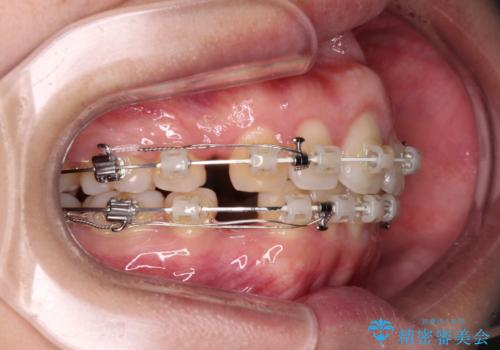

- 矯正装置

- 審美装置

- 1年8ヶ月

- 10-30回

口元を積極的に引っ込めるために、上下左右の小臼歯4本を抜歯することとしました。

咬み合わせが悪化することのないようにスペースを閉じていくことができ、比較的スムーズに治療を進めることができました。